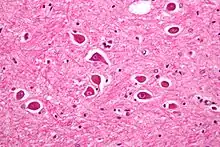

| Micrograph of Alzheimer type II astrocytes, as may be seen in hepatic encephalopathy | |

There are various explanations why liver dysfunction or portosystemic shunting might lead to encephalopathy. In healthy subjects, nitrogen-containing compounds from the intestine, generated by gut bacteria from food, are transported by the portal vein to the liver, where 80–90% are metabolised through the urea cycle and/or excreted immediately. This process is impaired in all subtypes of hepatic encephalopathy, either because the hepatocytes (liver cells) are incapable of metabolising the waste products or because portal venous blood bypasses the liver through collateral circulation or a medically constructed shunt. Nitrogenous waste products accumulate in the systemic circulation (hence the older term "portosystemic encephalopathy"). The most important waste product is ammonia (NH3). This small molecule crosses the blood–brain barrier and is absorbed and metabolised by the astrocytes, a population of cells in the brain that constitutes 30% of the cerebral cortex. Astrocytes use ammonia when synthesising glutamine from glutamate. The increased levels of glutamine lead to an increase in osmotic pressure in the astrocytes, which become swollen. There is increased activity of the inhibitory γ-aminobutyric acid (GABA) system and the energy supply to other brain cells is decreased. This can be thought of as an example of brain edema of the "cytotoxic" type.[13]